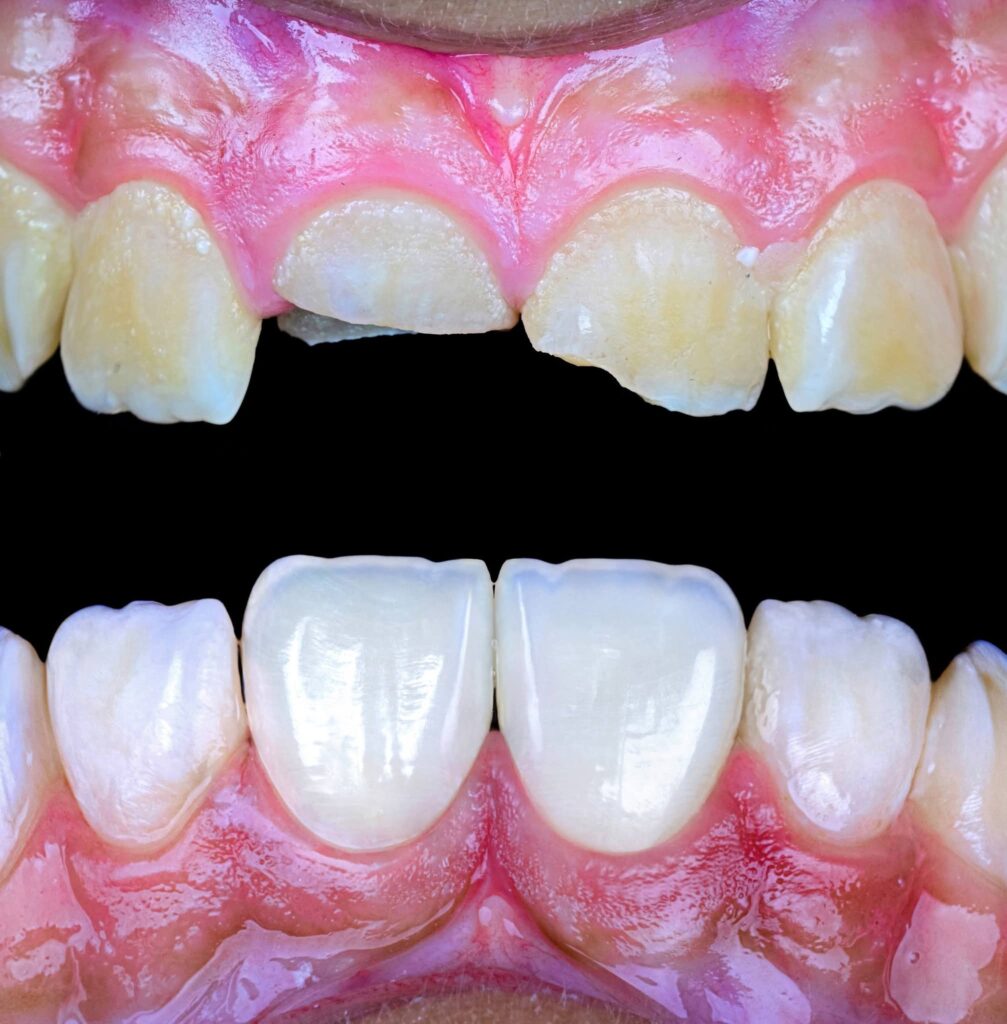

Symmetry and proportionality are fundamental principles in aesthetic dentistry, particularly in direct composite veneers, where the clinician acts simultaneously as a scientist and an artist. Successful veneers are not determined only by color and shape, but by the harmony between teeth, gingiva, lips, and face.

Symmetry refers to the mirror relationship between the right and left sides, especially the maxillary central incisors. Absolute symmetry is not always natural; therefore, perceived symmetry is more important than mathematical symmetry. Small differences in line angles, embrasures, and incisal edges can be used intentionally to create a natural appearance.

Proportionality relates to the width-to-length ratio and the relationship between anterior teeth. The ideal width/length ratio for central incisors is approximately 75–80%, and the apparent width proportion between anterior teeth often follows the golden proportion (~62%), although modern aesthetic dentistry prefers the concept of Recurring Esthetic Dental (RED) proportion for more natural results.